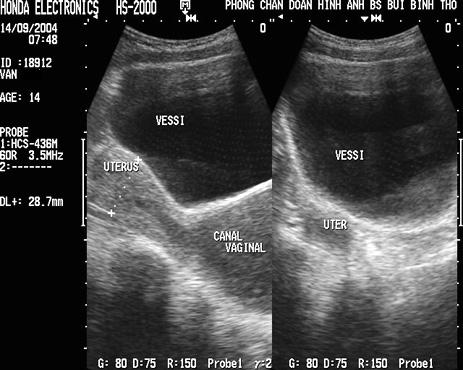

Cas : Jeune fille de 14 ans ,etre en

service par la douleur pelvienne et une retention urinaire provoquee

. Tumeur pelvienne palpable, fixe , situe a la

line medianne . Images echographiques donnait un vessi

de tres retention . Le canal vaginal a large dilate et la

liquide contenue est hypoechogene . Uterus en ce cas

est normal , mais le canal du col est dilate par la

retention en amont . |